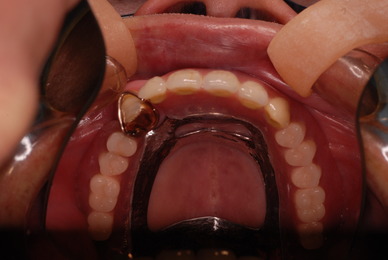

歯をいじられ体も心もボロボロになった患者さんからの手紙です。マスコミや権威などがいかにいい加減かわかります。歯は触らないほうがよろしいのです。

昭和60年代ぐらいから、私は歯を触るとか矯正するとかマウスピースをして顎の関節の症状を治癒するなどというような処置はしなくなってきました。

そもそも歯を触り何らかの金属やセラミックを入れる行為そのものが医学的には傷害処置ですから、なるべく避けるべき物なのです。